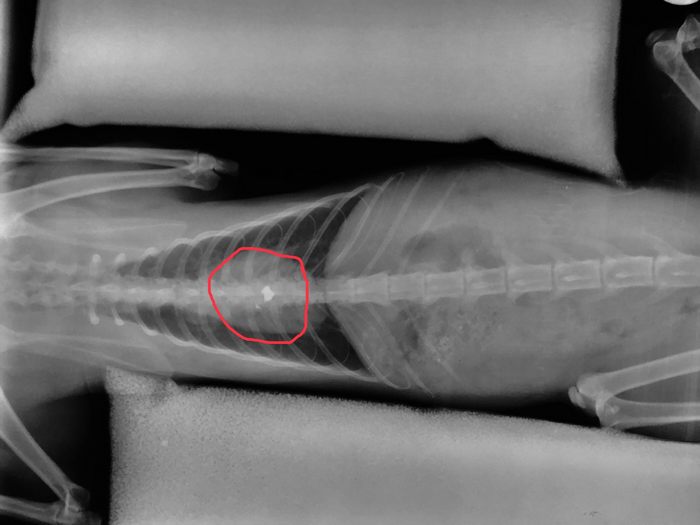

Σύμφωνα με τα όσα κατατέθηκαν ενώπιον των αστυνομικών και δικαστικών αρχών, ο εκπαιδευτικός που είναι και Λυκειάρχης σε σχολείο του δήμου Λαμιέων, πυροβόλησε το άτυχο ζώο με αεροβόλο, με τη βολίδα να σφηνώνεται στη σπονδυλική του στήλη και να μένει παράλυτο.

"Σε 16 μήνες φυλάκιση καταδικάστηκε σήμερα 12 Ιουλίου 2019 εκπαιδευτικός, διευθυντής σε Λύκειο της Δευτεροβάθμιας Εκπαίδευσης του Δήμου Λαμιέων, ο οποίος εν ψυχρώ πυροβόλησε και άφησε παράλυτο από την μέση και κάτω έναν αδέσποτο γάτο. Το άτυχο ζώο πυροβολήθηκε από τον δράστη με αεροβόλο όπλο την ώρα που ζευγάρωνε.